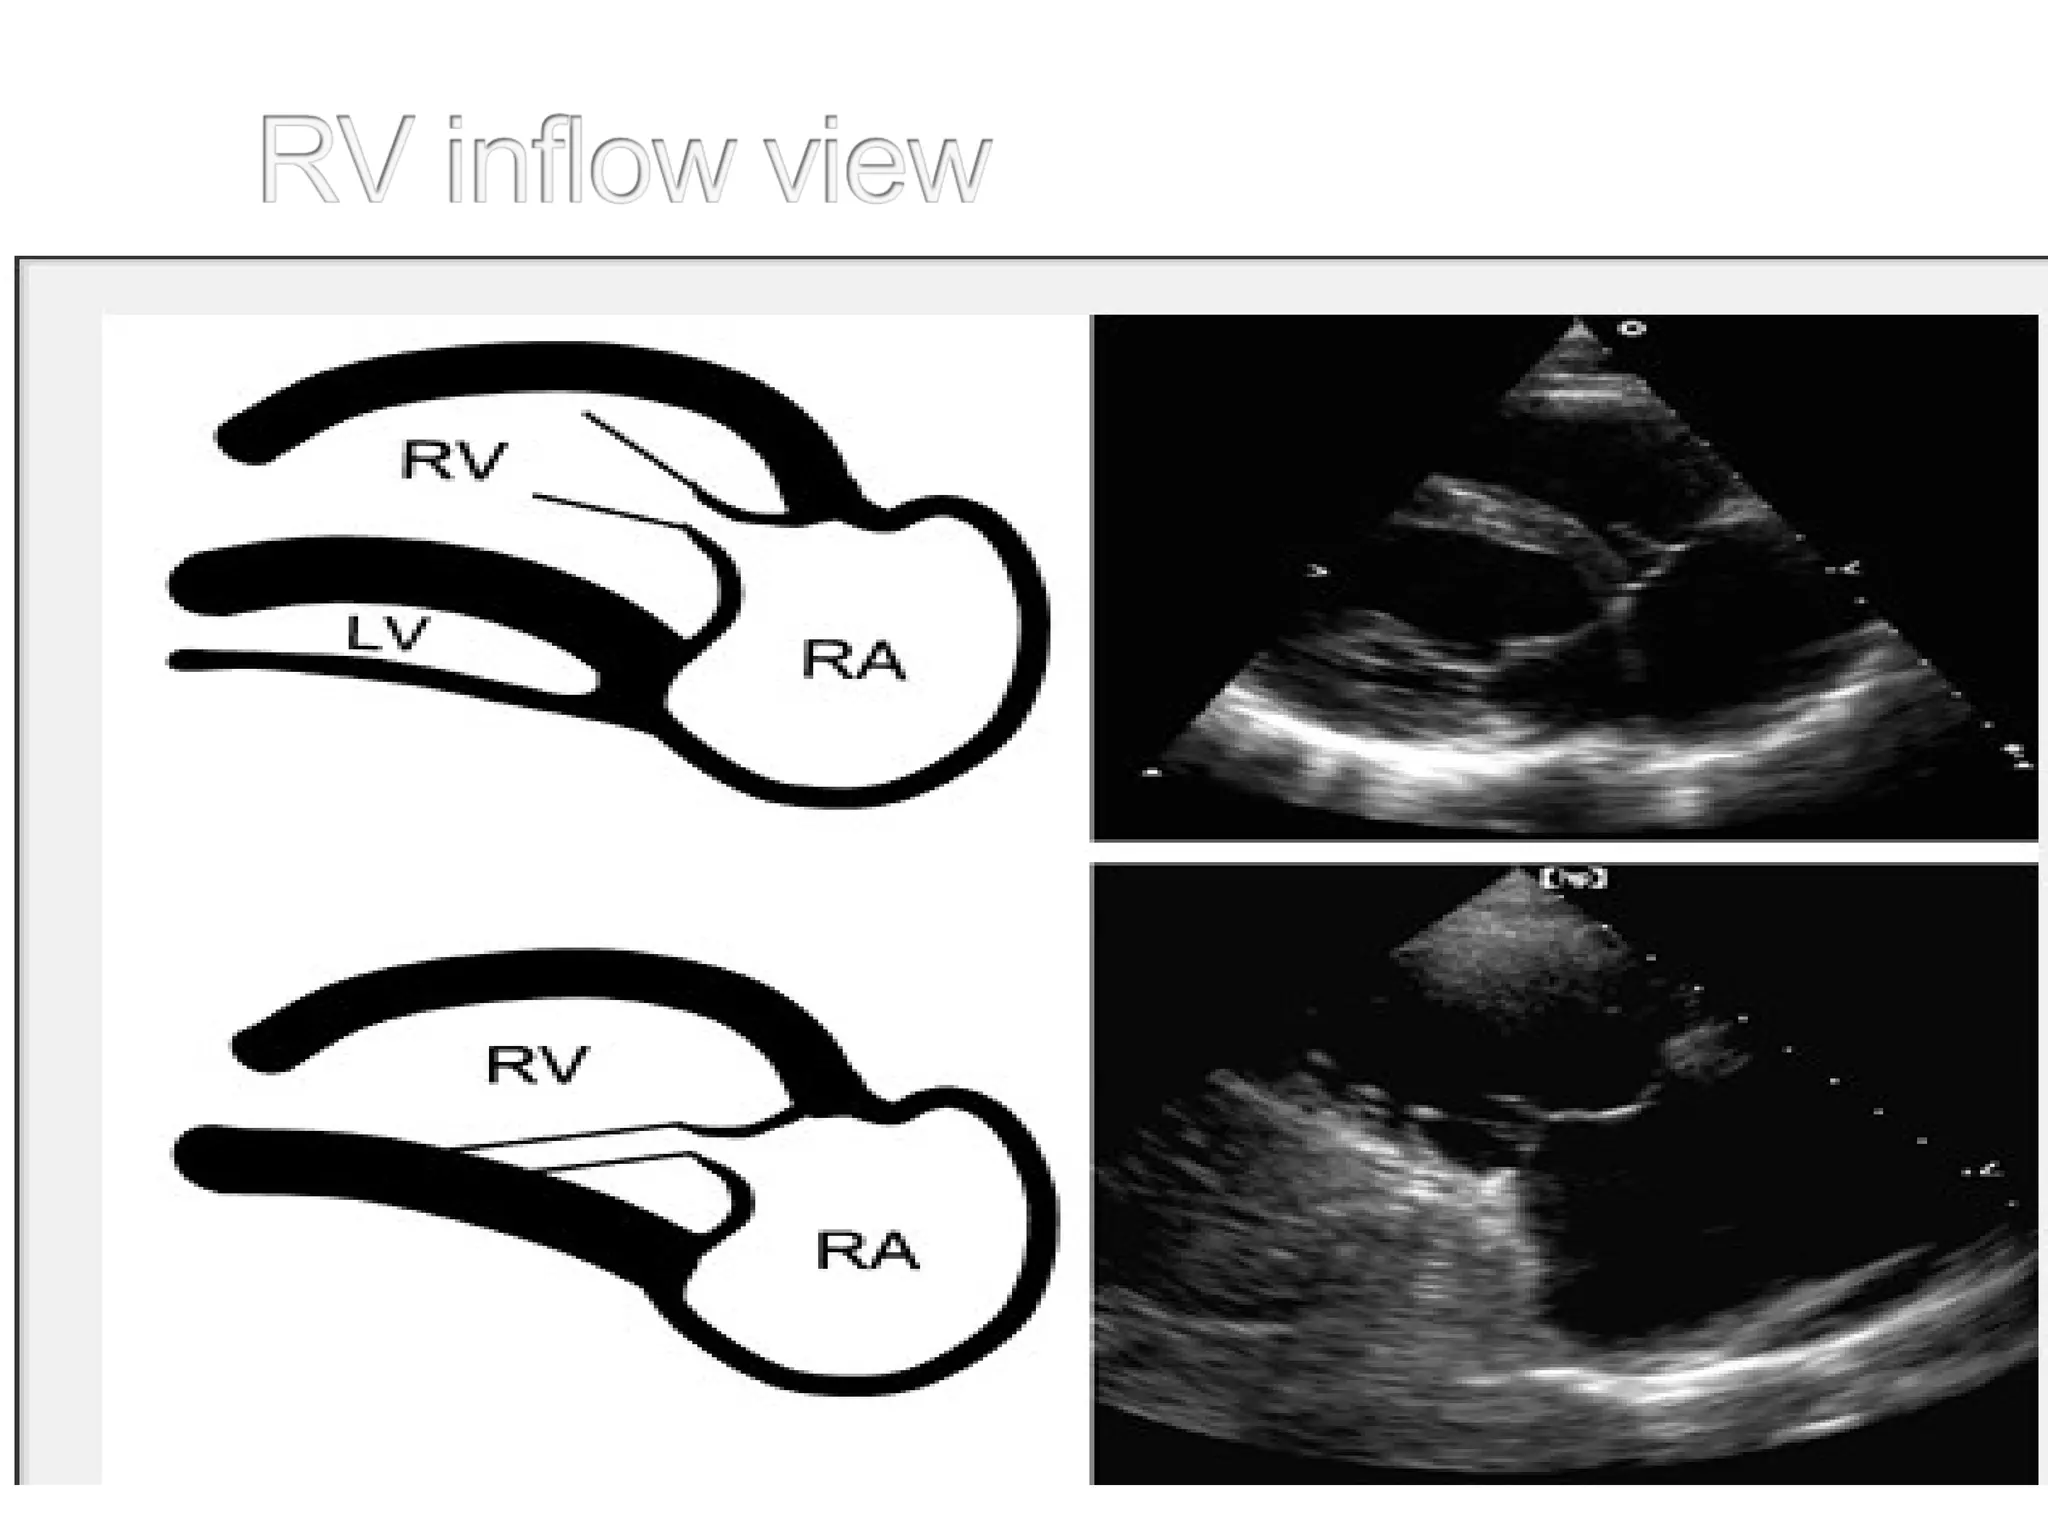

• Requires more than one position.

• Tilting pt to left improves ultrasound

windows.

• Rt lat decubitus-record aortic flow &

congen disease.

• Subcostal imaging

• Suprasternal notch

• Sitting position